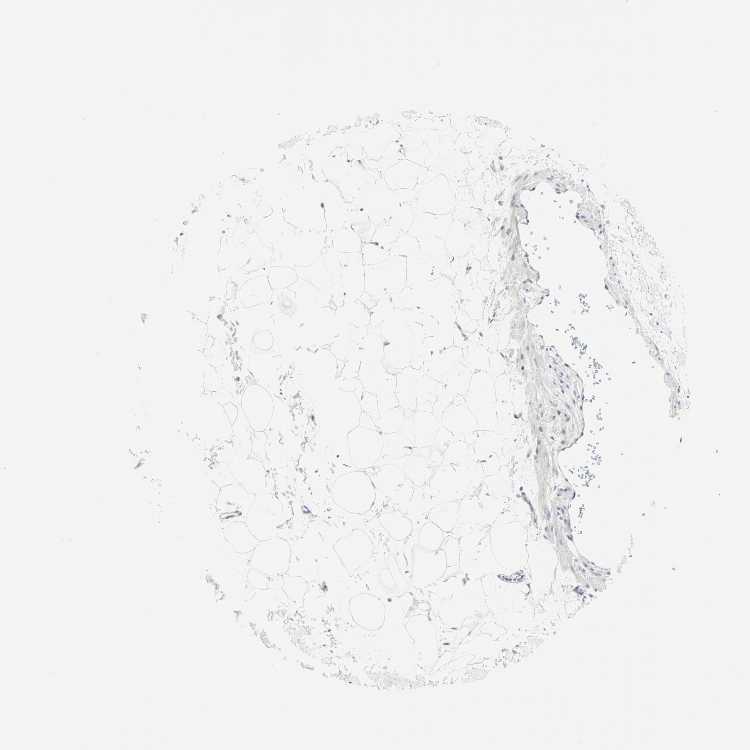

ADIPOSE TISSUE - Antibody stainingi

Antibody staining in the annotated cell types in the current human tissue is reported as not detected, low, medium, or high, based on conventional immunohistochemistry profiling in selected tissues. This score is based on the combination of the staining intensity and fraction of stained cells.

Each image is clickable and will lead to virtual microscopy that enables deeper exploration of all samples and also displays staining intensity scores, fraction scores and subcellular localization as well as patient and tissue information for each sample.

Antibody HPA061615Antibody CAB007786

Adipocytes Not detectedNot detected